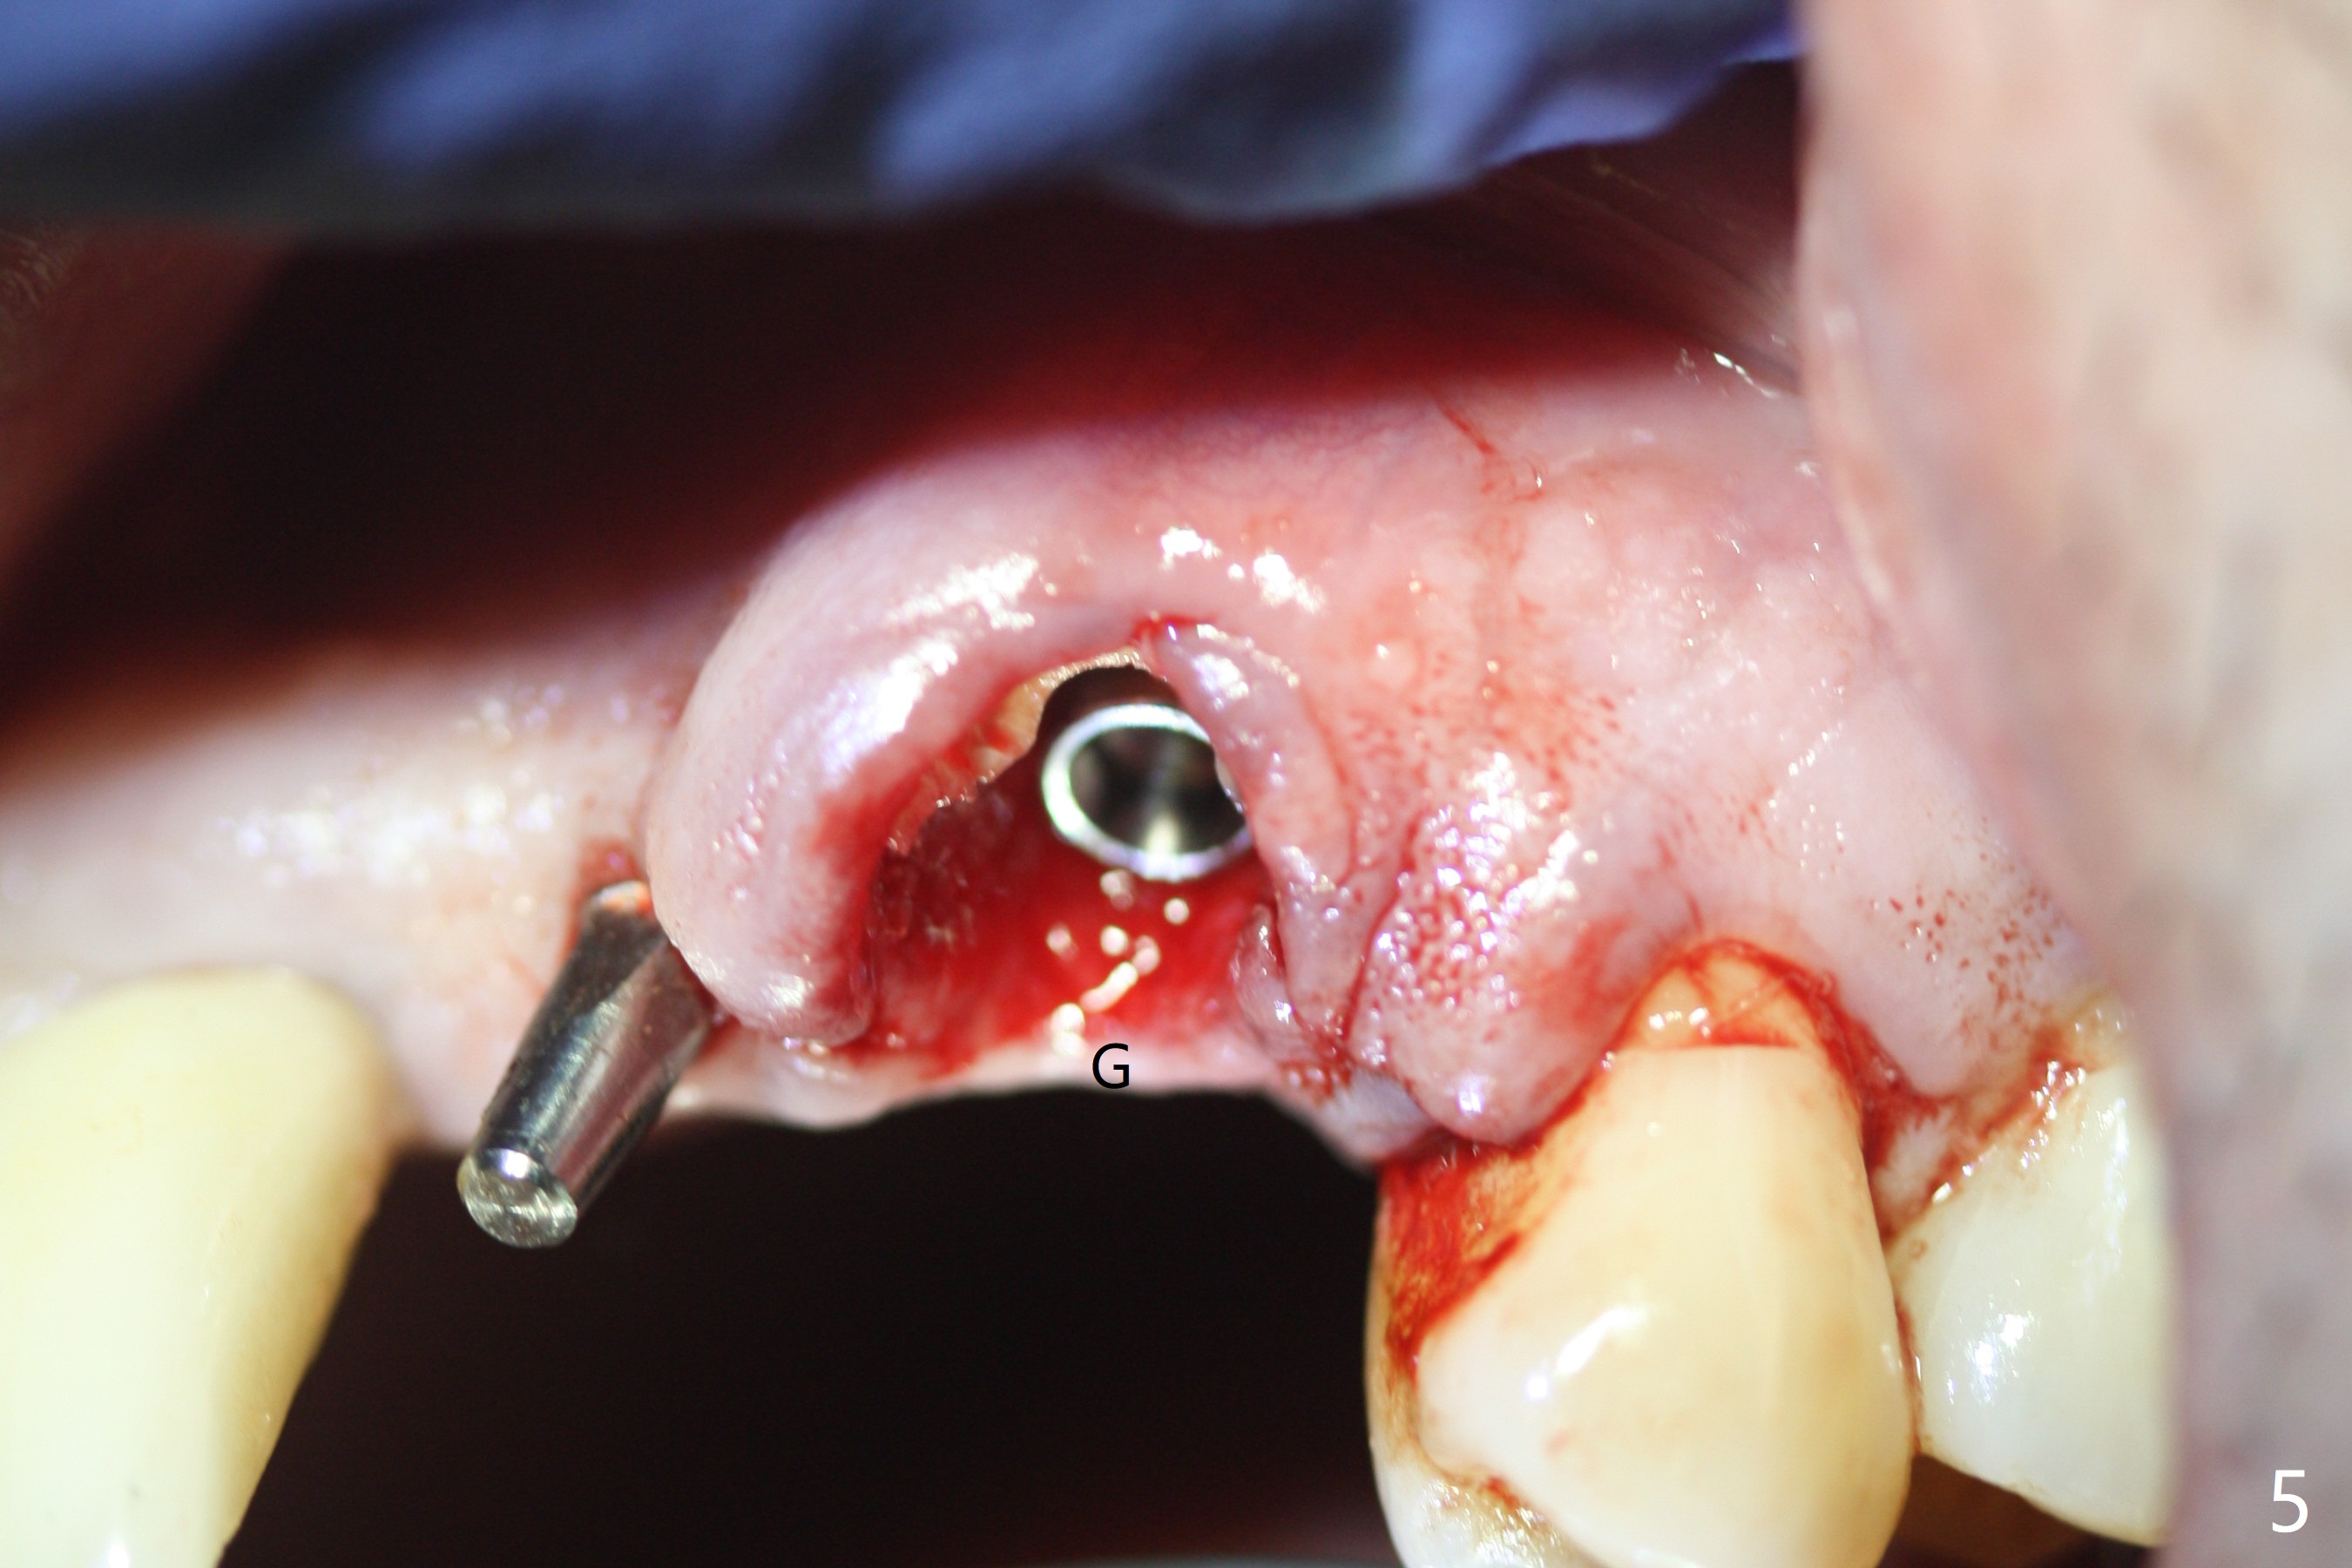

The buccal plate at #10 undergoes atrophy 9 months post immediate implant (Fig.1 *). To prevent the same post-extraction complication at #11, a technique called socket shield is going to be adopted. The buccal portion of the root (Fig.2-6 R, half-moon shaped) remains in place while a 3.5x13 mm implant is placed in the palatal portion of the socket (>50 Ncm). In fact the root is trimmed slightly subcrestal (Fig.6 C). It is assumed that there will be no or minimal bone resorption as long as the periosteum between the buccal plate and the remaining buccal root is not disturbed after tooth removal. After placement of a 4.5x15 degrees A (2mm) angled abutment and Vanilla graft (Fig.7 *), an immediate provisional is fabricated (using a central incisor crown form for #10 because of extra wide space of #11, Fig.8). There is no buccal plate atrophy at the canine 11 days postop (Fig.9). There is smooth transition from the grafted bone to the native bone 4.5 months postop (Fig.10). The buccal plate remains non-atrophic at the canine 4.5 months postop (Fig.11,12). CT taken 1 month post cementation shows that the implants at #10 and 11 are placed somewhat lingually (Fig.13,14 L (*: socket shield)). Gingival swelling is noted (Fig.15 *) with +Bleeding On Probing (^) 8 months post cementation (at the time of #21/24 impression). It appears that the socket shield (Fig.16 S) causes infection and loss of bone graft (*). The shield will be removed with an oblique accessory incision to save the papilla between #10 and 11 (Fig.17 black line). Prepare PRF for sticky bone (x1).